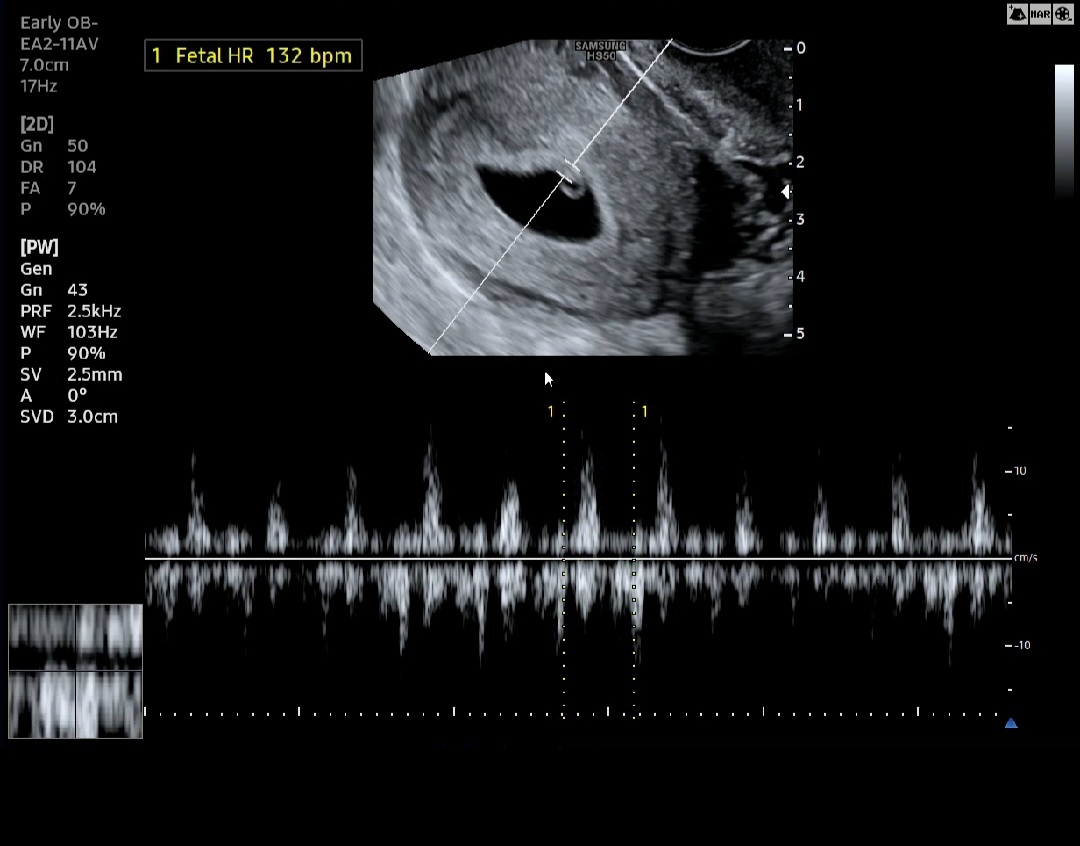

6주2일 심소 듣고 왔어요 ☺️

심소 못들을까바 너무너무너무너무 걱정했는데 피고임도 없고 건강한 우리 애기 심장소리 듣고 왔어요 소리 듣는데 뭔가 맘 한쪽에 울컥 하는 감정이..